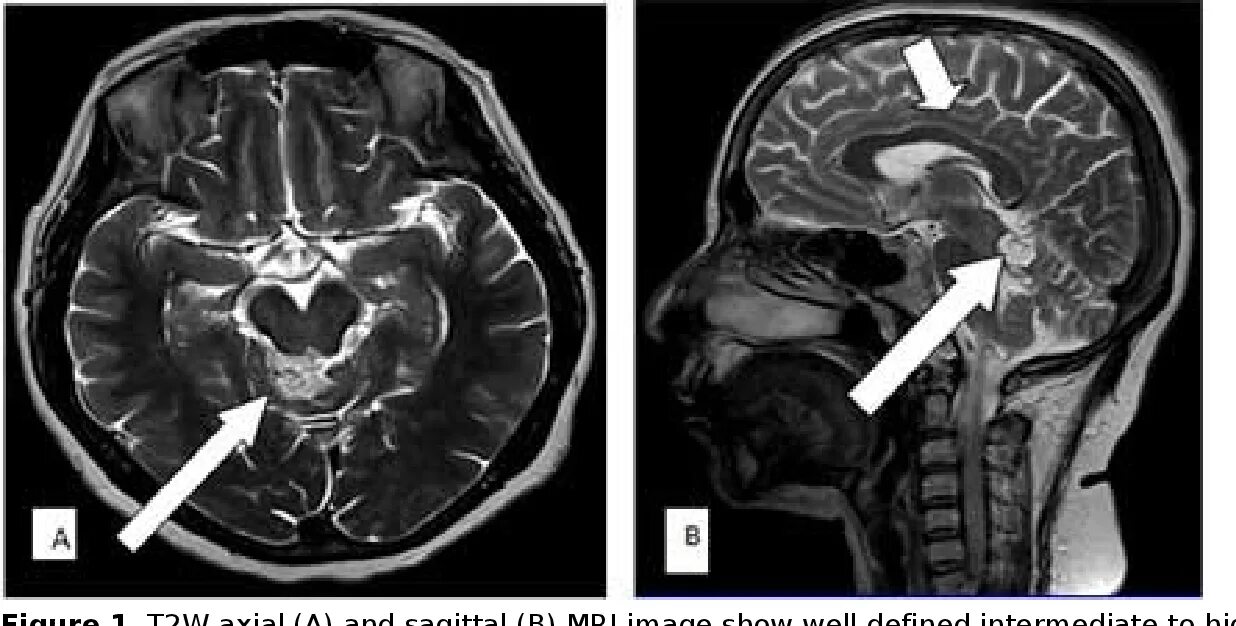

Цистерны на кт